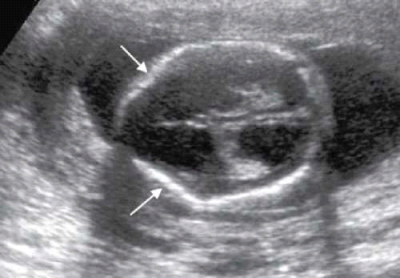

בבדיקת על-שמע בשליש השני להיריון נראה סימנים אופייניים למום בתעלה העצבית:

- סימן לימון (Lemon sign): שקיעה של העצמות המצחיות (Frontal). בתמונה רואים גם הגדלה של חדרי המוח (Ventriculomegaly);

- סימן בננה (Banana sign): בקיעה (Herniation) של המוחון והשטחה של הבְּרֵכָה הגדולה (Cisterna magna).

בכל המקרים נראה הגדלה של חדרי המוח וקוטר דו-קודקודי (BPD, Biparietal Diameter) קצר.